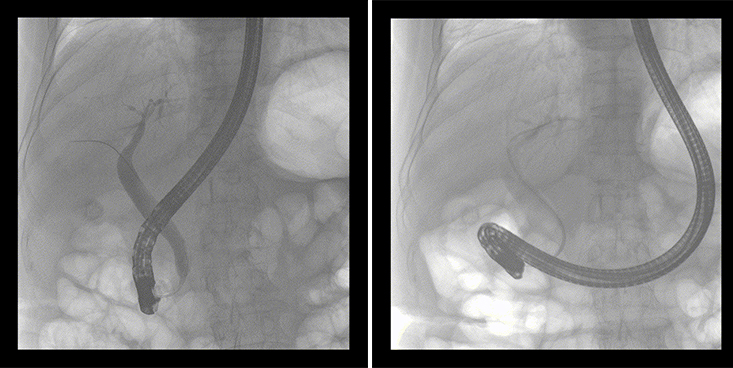

一位86歲的女性患者近來(lái)出現(xiàn)腹痛,入院后CT檢查并結(jié)合臨床表現(xiàn)被診斷為急性膽囊炎伴膽囊結(jié)石。經(jīng)專家團(tuán)隊(duì)協(xié)商并與患者家屬溝通,決定對(duì)患者實(shí)施經(jīng)內(nèi)窺鏡逆行胰膽管造影(ERCP)。

ERCP(經(jīng)十二指腸鏡下逆行胰膽管造影)現(xiàn)已成為比較成熟的微創(chuàng)介入技術(shù),被廣泛的應(yīng)用于臨床,ERCP也是消化內(nèi)鏡領(lǐng)域難度大、風(fēng)險(xiǎn)大、技術(shù)復(fù)雜的微創(chuàng)手術(shù),其并發(fā)癥多為致命性,ERCP手術(shù)對(duì)醫(yī)生的要求很高,因此,ERCP醫(yī)生又被稱為“刀尖上的舞者”。因?yàn)槭中g(shù)難度較大,過程復(fù)雜,需要C形臂精準(zhǔn)的配合,對(duì)影像清晰度的要求也非常高。

普愛醫(yī)療移動(dòng)式平板中C為本次ERCP手術(shù)提供實(shí)時(shí)無(wú)損高清影像,幫助醫(yī)生精準(zhǔn)定位。“成像效果非常棒!完全不輸國(guó)際大牌的醫(yī)學(xué)影像設(shè)備……”鼓樓醫(yī)院江北國(guó)際醫(yī)院內(nèi)鏡中心手術(shù)團(tuán)隊(duì)對(duì)普愛醫(yī)療移動(dòng)式平板中C的成像效果給與了高度的評(píng)價(jià)。

在消化內(nèi)科主任的領(lǐng)導(dǎo)和多科室全力配合下,南京鼓樓醫(yī)院江北國(guó)際醫(yī)院成功完成了首例ERCP手術(shù)。